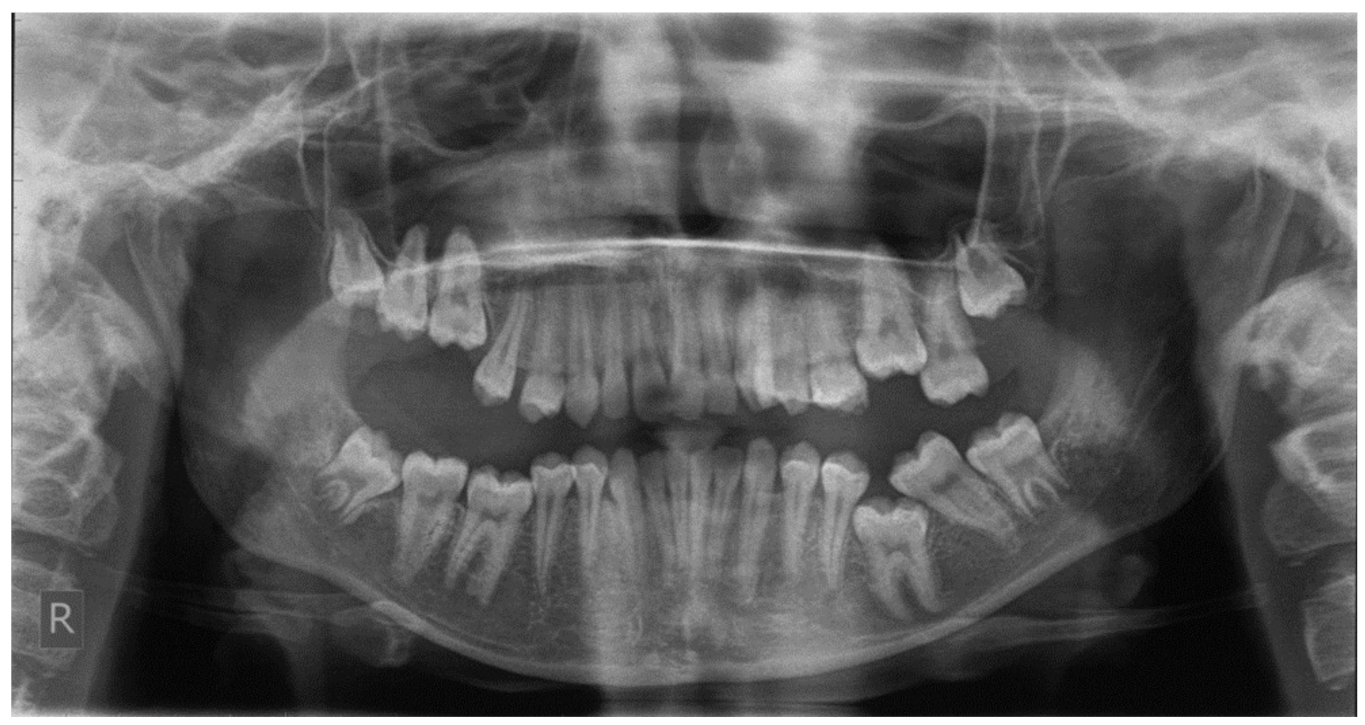

Figure 5.

Right photo of the female patient with PFE in bite relationship.

Open bite is present at the right posterior segment due to the impaction of the upper and lower left first molars.

Figure 5 and Figure 6 present a PFE case of a 17-year-old female patient referred to the Orthodontic Clinic of the Dental School of the National and Kapodistrian University of Athens, Greece. Clinical examination showed a posterior open bite on the right segment, as well as infraoccluded left upper and lower first molars. The patient’s orthopantomography shows no visible PDL of the right upper and lower first molars or the teeth distally related to them.